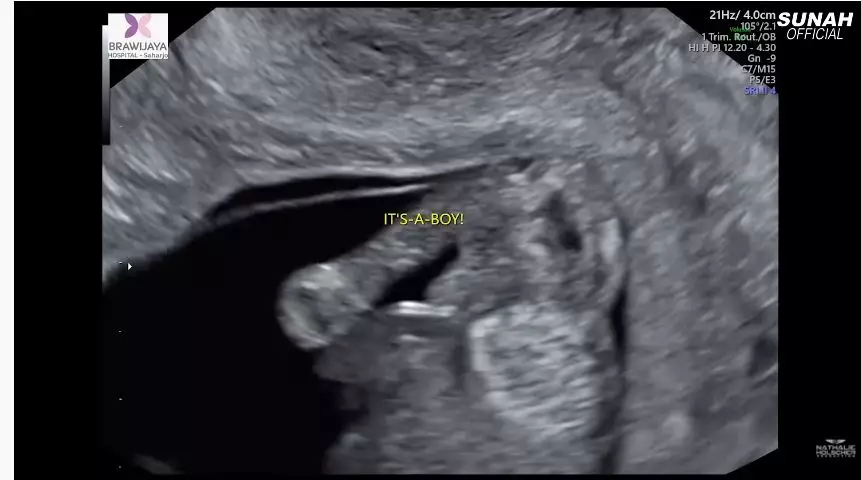

3. Sesampainya di rumah sakit, Nathalie pun langsung melakukan USG untuk melihat perkembangan janinnya.

6. Sule pun diajak untuk menebak janin yang dikandungnya. Dan ternyata, buah hati yang tengah dikandung oleh Nathalie Holscher berjenis kelamin laki-laki.

10. Selamat ya, Sule dan Nathalie. Semoga si baby boy di dalam kandungan sehat selalu!